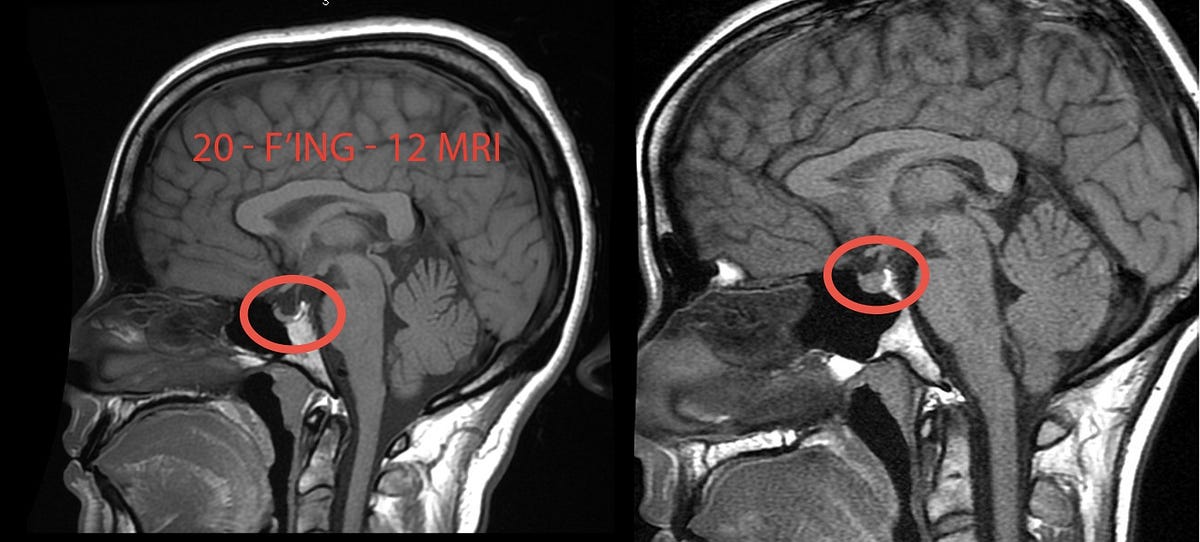

2. Empty sella turcica on MRI brain Download Scientific Diagram

Figure 2 from 'Empty sella' on routine MRI studies An incidental

Partially Empty Sella Turcica